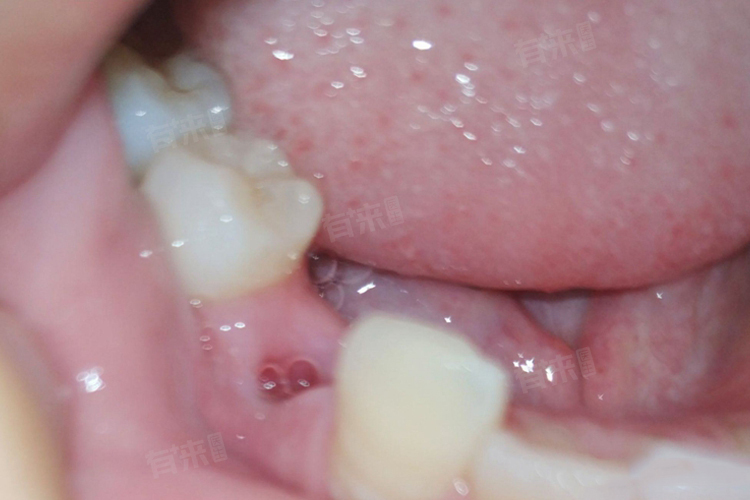

2、拔牙创口情况:

- 当拔牙过程复杂,如阻生齿拔除、创口较大或伴有感染时,镶牙时间需适当延迟。这类情况通常在拔牙后4-6个月,待创口完全愈合、牙槽骨形态稳定后,再根据修复方式确定具体镶牙时间,以避免因创口未愈影响修复效果。